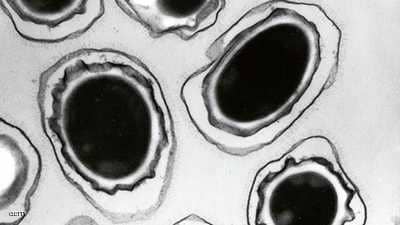

قال مسؤولون في مجال الصحة إنه لا يوجد مؤشر على تباطؤ انتشار البكتيريا الخارقة، أي المقاومة للمضادات الحيوية، في أوروبا، مما قد يزيد صعوبة علاج التسمم الغذائي وغيره من أشكال العدوى.

وتتطور المقاومة للدواء بفعل إساءة استخدام المضادات الحيوية وغيرها من الأدوية المضادة للميكروبات، أو الإفراط في استخدامها، الأمر الذي يشجع البكتيريا على التطور من أجل البقاء بإيجاد طرق جديدة للتغلب على الدواء.

وخلص التقرير إلى أن مقاومة بكتيريا تعرف باسم “كامبيلوباكتر”، ويمكن أن تصيب الإنسان بالتسمم الغذائي، لأحد المضادات الحيوية شديدة في بعض الدول، لدرجة أن هذه الأدوية لم تعد فعالة في علاج الحالات الخطيرة.

وأضاف التقرير أن معظم الدول قالت إن مقاومة بكتيريا “سالمونيلا” التي تصيب البشر للمضاد الحيوي “فلوروكينولونيز” تزداد، كما أن مقاومة 3 أو أكثر من مضادات الميكروبات شديدة في بكتيريا “سالمونيلا” التي تصيب البشر والحيوانات.